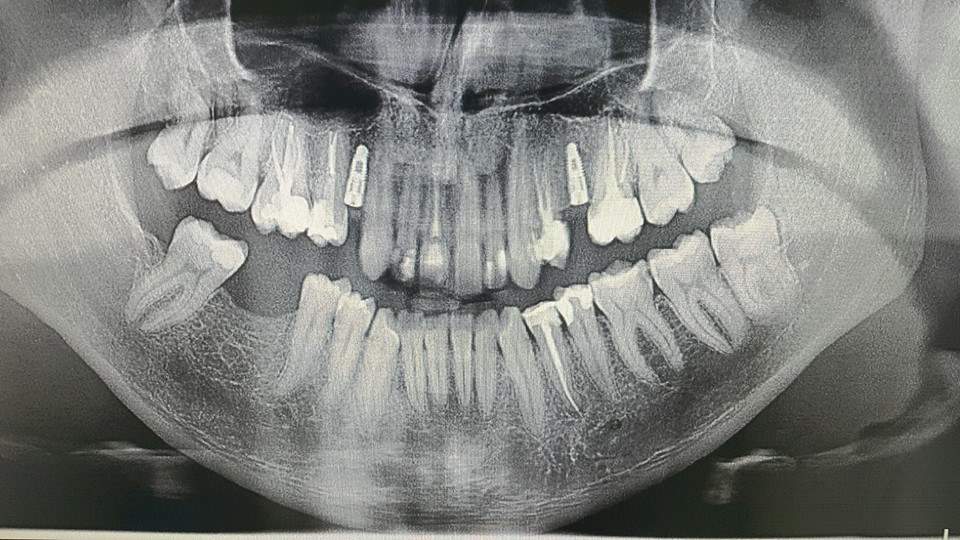

Nedostatak zuba, gornjeg desnog prvog premolara i gornjeg lijevog drugog premolara, nadoknađen je ugradnjom implantata a u gornjem frontu postavljene su estetske bezmetalne krunice.